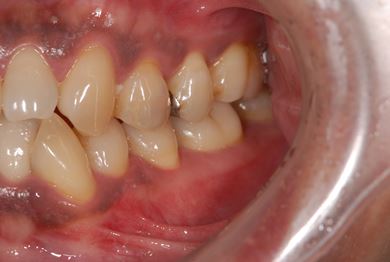

セラミック治療+歯肉歯槽骨整形術

| 性別/年齢 | 男性 / 45歳 | ||||||||||||||||||||||||||||||||

| 主訴 | 詰め物をしている歯が割れてしまったので、治療して欲しい。 | ||||||||||||||||||||||||||||||||

| 治療方針 | セラミック治療にて、審美的回復を行う。 | ||||||||||||||||||||||||||||||||

| 治療内容 | メタルボンドセラミッククラウン1本(メタルボンドセラミック用土台1本)、歯肉歯槽骨整形手術 | ||||||||||||||||||||||||||||||||

| 総治療費 | 157,185円 | ||||||||||||||||||||||||||||||||

| 治療期間 | 7ヶ月 |